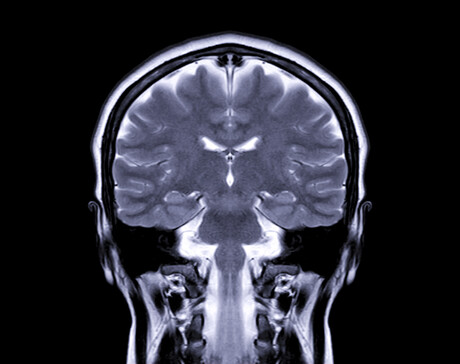

Alzheimer’s is the most common form of dementia, accounting for 60–80% of cases. One of the ways of measuring its progress is via magnetic resonance imaging (MRI) that shows cortical thinning, which can start up to 10 years before clinical symptoms of Alzheimer’s appear. Such measurement is challenging, however, as changes in the thickness of the brain’s cortex are extremely small, often in the submillimetre range.

“Using the power of machine learning, we were able to produce a set of artificial MRI images of brains with predefined signs of neurodegeneration in the cortex region, the outer layer of the brain most affected by Alzheimer’s.

The new technique allows researchers to set the amount and location of brain degeneration they want to compare against so they can get a clear picture of what method of cortical thickness quantification performs the best. It can test the sensitivity of methods to a minuscule level, determining whether a method can detect changes in thickness of just 0.01 mm.